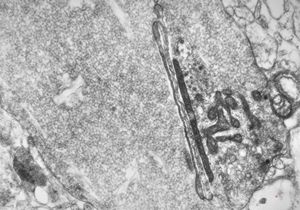

F,50y. | progressive multifocal leukoencephalopathy- viral particles in a glial cell

F,50y. | progressive multifocal leukoencephalopathy- viral particles in a glial cell

F,50y. | progressive multifocal leukoencephalopathy- viral particles in a glial cell